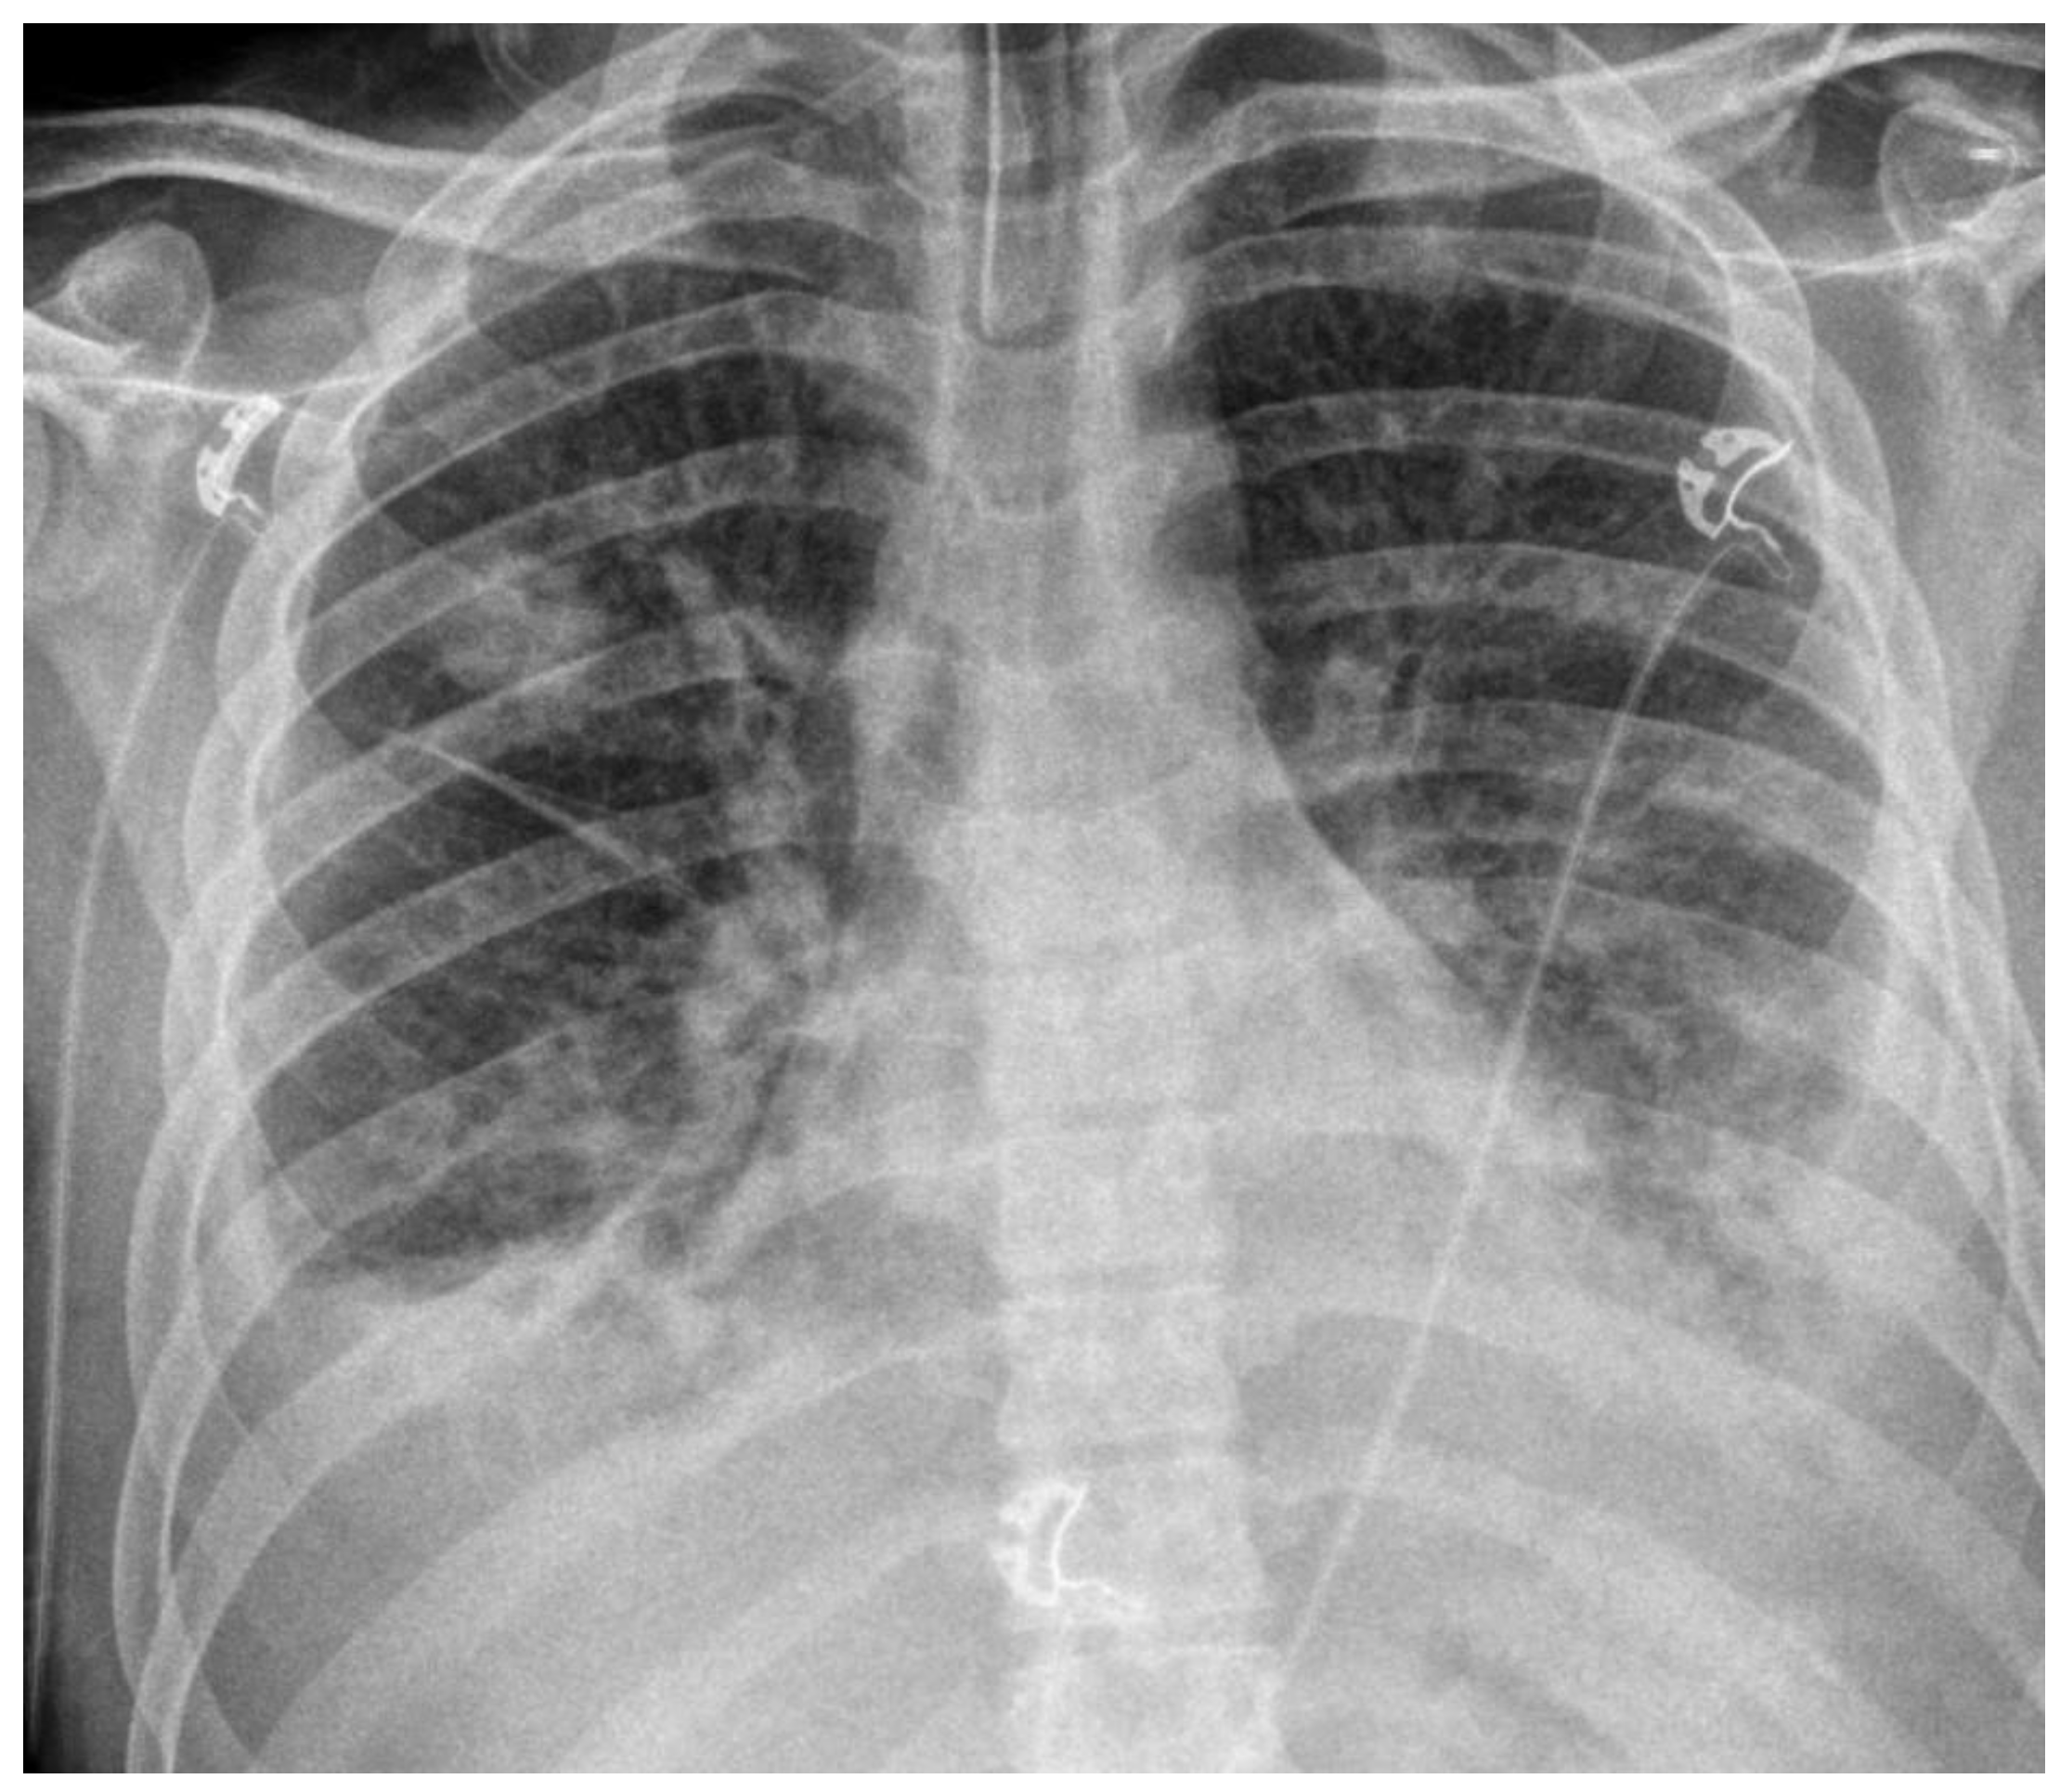

Case Presentation: